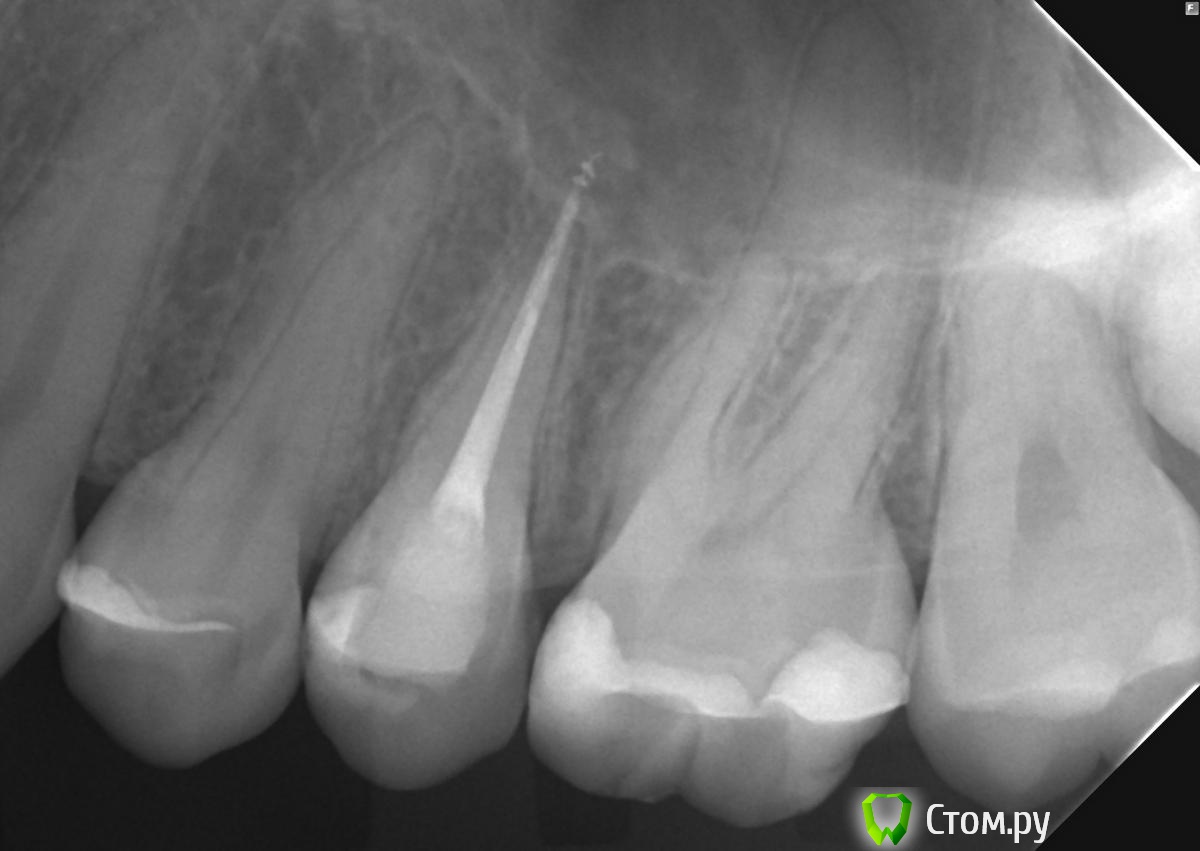

felicidade Опубликовано 19 июня, 2014 Автор Поделиться Опубликовано 19 июня, 2014 Прощу прощение, но только сейчас вспомнила, что у меня имеется апрельская ОПТГ, там вроде бы как раз 25й зуб виден немного под другим углом. Новый снимок, я, безусловно, сделаю, но, может, пока и благодаря ОПТГ что-то уже становится яснее?.. http://i062.radikal.ru/1406/42/8de5c832a66e.jpg Ссылка на комментарий

DokDent Опубликовано 19 июня, 2014 Поделиться Опубликовано 19 июня, 2014 похоже что всё-таки 2 Ссылка на комментарий